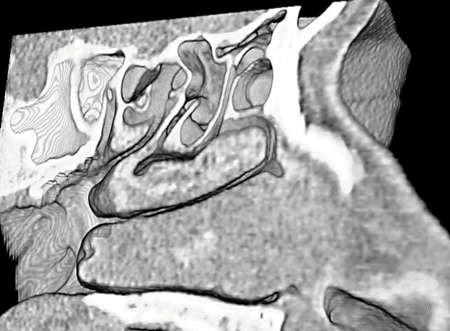

Both Dr Kennedy and Dr Stammberger influenced my selection of the CT images needed to meet the surgical requirements. Most memorable for me was the time spent at one of the earlier AAO meetings in San Antonio, where Dr Stammberger and I spent countless hours establishing the course of the basal lamella of the middle turbinate, a concept well-displayed in his drawings of the structure. This concept, as well as others, is demonstrated with standard orthogonal, multiplanar reconstructions and with the 3D surface rendered images ‘scattered’ throughout his famous text book. Dr Stammberger used his excellent educational skills to optimal advantage when he illustrated his message with concrete and detailed imaging, thereby informing the reader of the essence of sinus surgery, and the information needed for its optimal performance [2-4].

Evolution of sinus imaging: (Figure A) X-ray polytomography; (Figure B) Coronal CT scan; (Figure C) CT MPR and surface-rendered 3D image; (Figure D) 3D CT Stereoscopic Image showing the anatomy in the sagittal plane.

At the Endo Chicago 2016 meeting, Dr Stammberger and I discussed the need to establish imaging landmarks based on the lamellar principles that were the subject of his lectures. The discussion continued in Stockholm at the ERS meeting, and then later, at the AAO-HNS meeting, that same year. By the time we met in San Diego, I was able to show him preliminary 3D CT stereoscopic images we were creating at Hopkins. He was amazed, as he looked at the 3D stereographic images that provided information which, for the first time, resembled the actual anatomy. As we studied the images, he was convinced that the new technology would provide a new look and an improved understanding of the individually complex sinus anatomy.